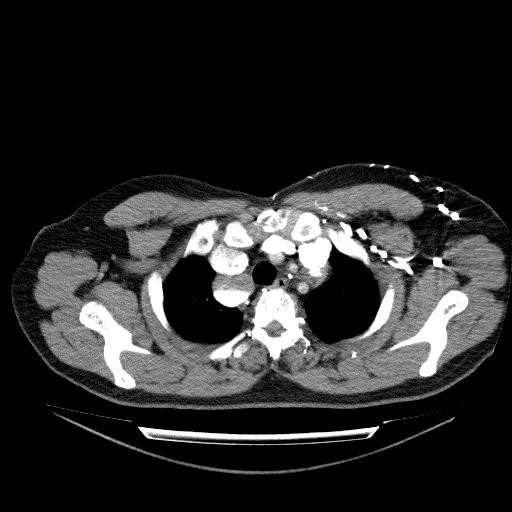

Timusda kütlənin olub olmadaığını dəqiqləşdirmək üçün KT və ya MRT lazımdır (Şəkil 26,27).

Şəkil 26. KT. Timoma

Şəkil 27. KT. Timoma